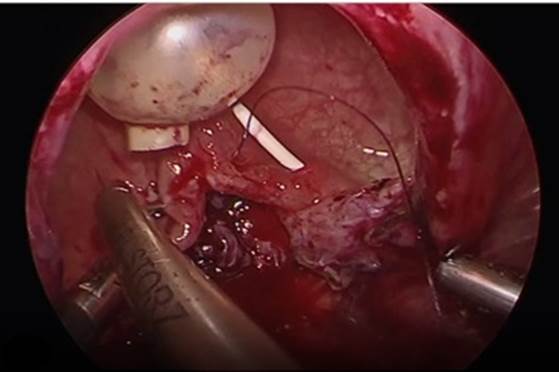

7. Cierre de la vagina y vejiga. El cual se realiza de forma separado en dirección horizontal de la vagina (Fig. 10) y vertical de la vejiga con monocryl 2-0 (Fig. 11).

8. Interposición de tejido. Se moviliza parche de epiplón, o apéndice epiplóico y se coloca entre ambos planos, vaginal y vesical, fijándose con ácido poliglicólico. Se coloca un drenaje pélvico tipo Penrose de 0.5 pulgadas través de un puerto de 5 mm y se dirige al sitio de cistorrafia, se retiran trócares y se da por terminado el procedimiento.